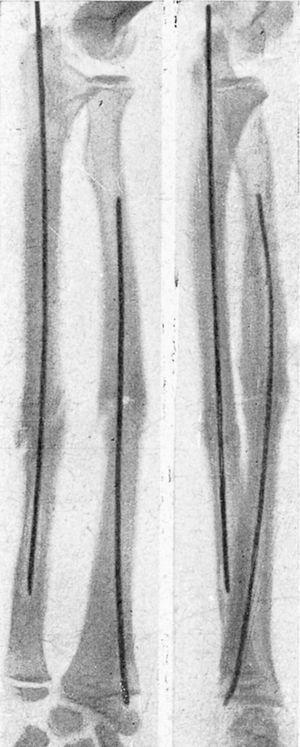

Figura 2. Fractura transversal tercio medio tibia, sin desviación, peroné íntegro, enclavijamiento cerrado; fue uno de los primeros casos tratados, y a los tres meses reanudaba el trabajo; un solo clavo mantuvo una perfecta inmovilización.

Figura 3. Fractura tercio medio tibia y peroné; enclavijamiento cerrado con un solo clavo; un tercer fragmento impide la exacta coaptación de fragmentos, obteniéndose, no obstante, una buena consolidación con predominio de callo periostal; se aprecia en la parte superior el orificio de la trepanación de entrada del clavo.